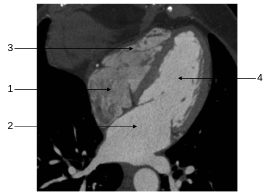

Fig. 35.2 Coupe axiale transverse thoracique passant par l’artère pulmonaire gauche.

1. Veine cave supérieure. 2. Aorte ascendante. 3. Artère pulmonaire gauche. 4. Veine pulmonaire supérieure gauche. 5. Aorte descendante.

Source : CERF, CNEBMN, 2022.